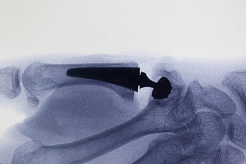

X-Ray’ler genellikle OA’yı doğrulayacaktır (Şekil A).